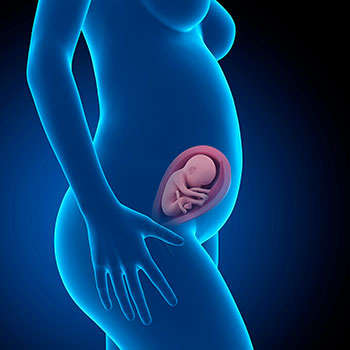

Na 26ª semana de gravidez o teu bebé já mede cerca de 35 centímetros da cabeça ao coxis e pesa cerca de 760 gramas.

Nestas semanas vai colocar-se na denominada “posição fetal”: a cabeça fletida sobre o tórax, os braços também fletidos, as mãos apoiadas no peito e os joelhos bem dobrados sobre a barriga.

Não tem muito espaço, mas isso não o impede de se mexer. De facto, encontra-se numa fase especialmente ativa. O líquido amniótico que o rodeava vai reduzindo proporcionalmente ao aumento do seu tamanho e agora os movimentos do bebé podem ser visíveis, até, na superfície do abdómen.

Idade do feto: 24 semanas.